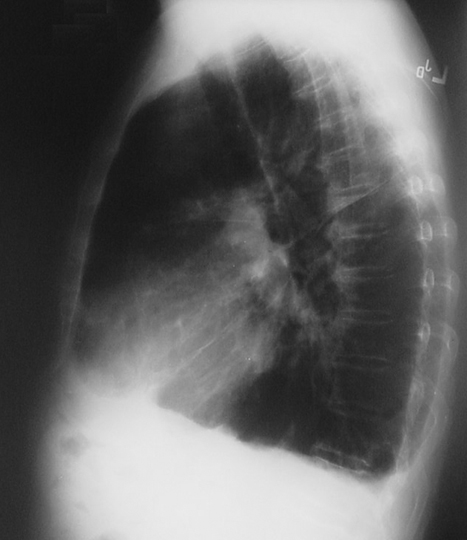

Image 3.1

The chest radiograph in posterior-anterior view above and lateral view below demonstrates a marked increase in size of the chest cavity. Note the increased lucency due to the loss of lung parenchyma. There is prominence of the pulmonary arteries at the hila, indicative of pulmonary hypertension. |